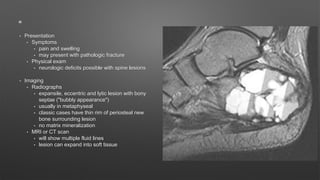

• Presentation

• Symptoms

• pain and swelling

• may present with pathologic fracture

• Physical exam

• neurologic deficits possible with spine lesions

• Imaging

• Radiographs

• expansile, eccentric and lytic lesion with bony

septae ("bubbly appearance")

• usually in metaphyseal

• classic cases have thin rim of periosteal new

bone surrounding lesion

• no matrix mineralization

• MRI or CT scan

• will show multiple fluid lines

• lesion can expand into soft tissue